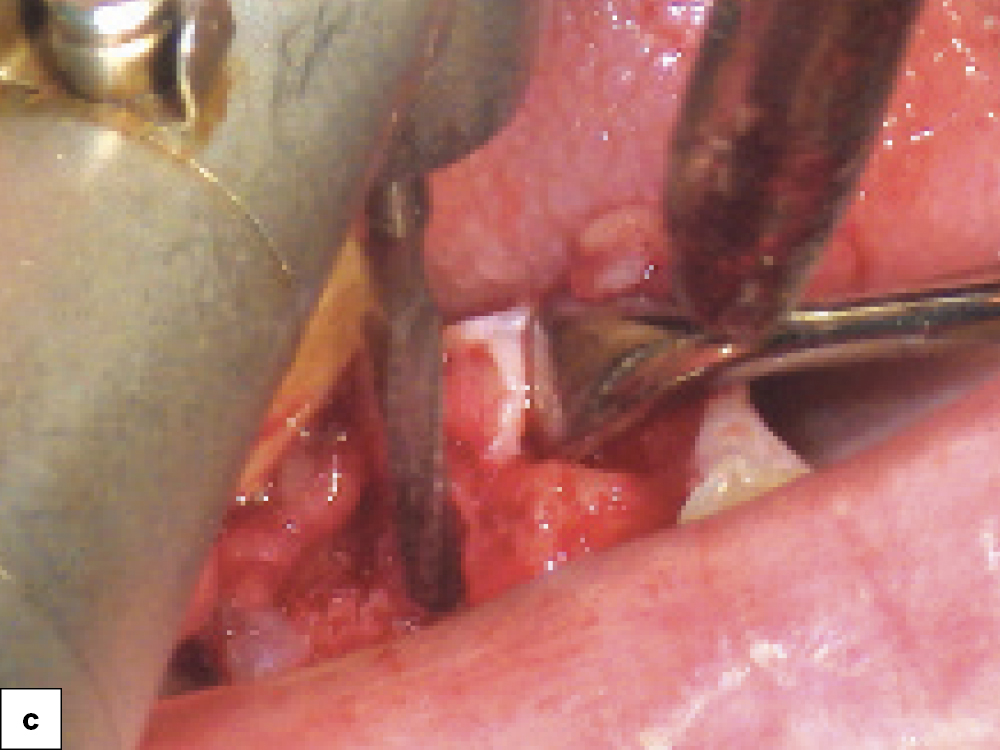

Extraction Socket

Implant Freehand Placement

Hahn Tapered Implant Visual

Provided that sufficient primary stability and proper positioning can be achieved, placing an implant during the same appointment the defect is grafted reduces the number of surgical appointments. Here, a Hahn Tapered Implant was placed freehand into an extraction socket with a bony defect. The sharp, pronounced threads of the implant helped keep the implant engaged with the lingual bone, which is essential in avoiding any further damage to the buccal plate. After positioning a Newport Biologics™ Resorbable Collagen Membrane 4–6 (Glidewell Direct), the gaps between the bone and implant were filled with allograft. The surface of the buccal plate was also grafted prior to suturing.